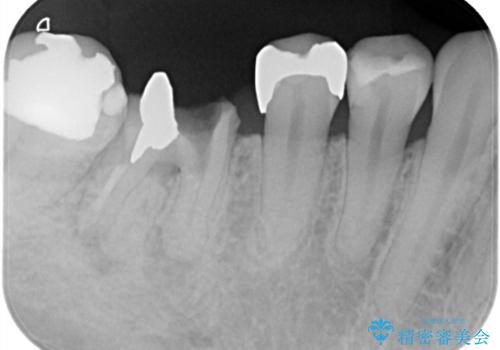

- 右下奥歯が虫歯で被せ物が取れてしまい、また噛めるようにしたいとのことで来院されました。

虫歯が大きく、歯を保存することが難しい状態でしたので、抜歯してインプラント治療を行うこととなりました。